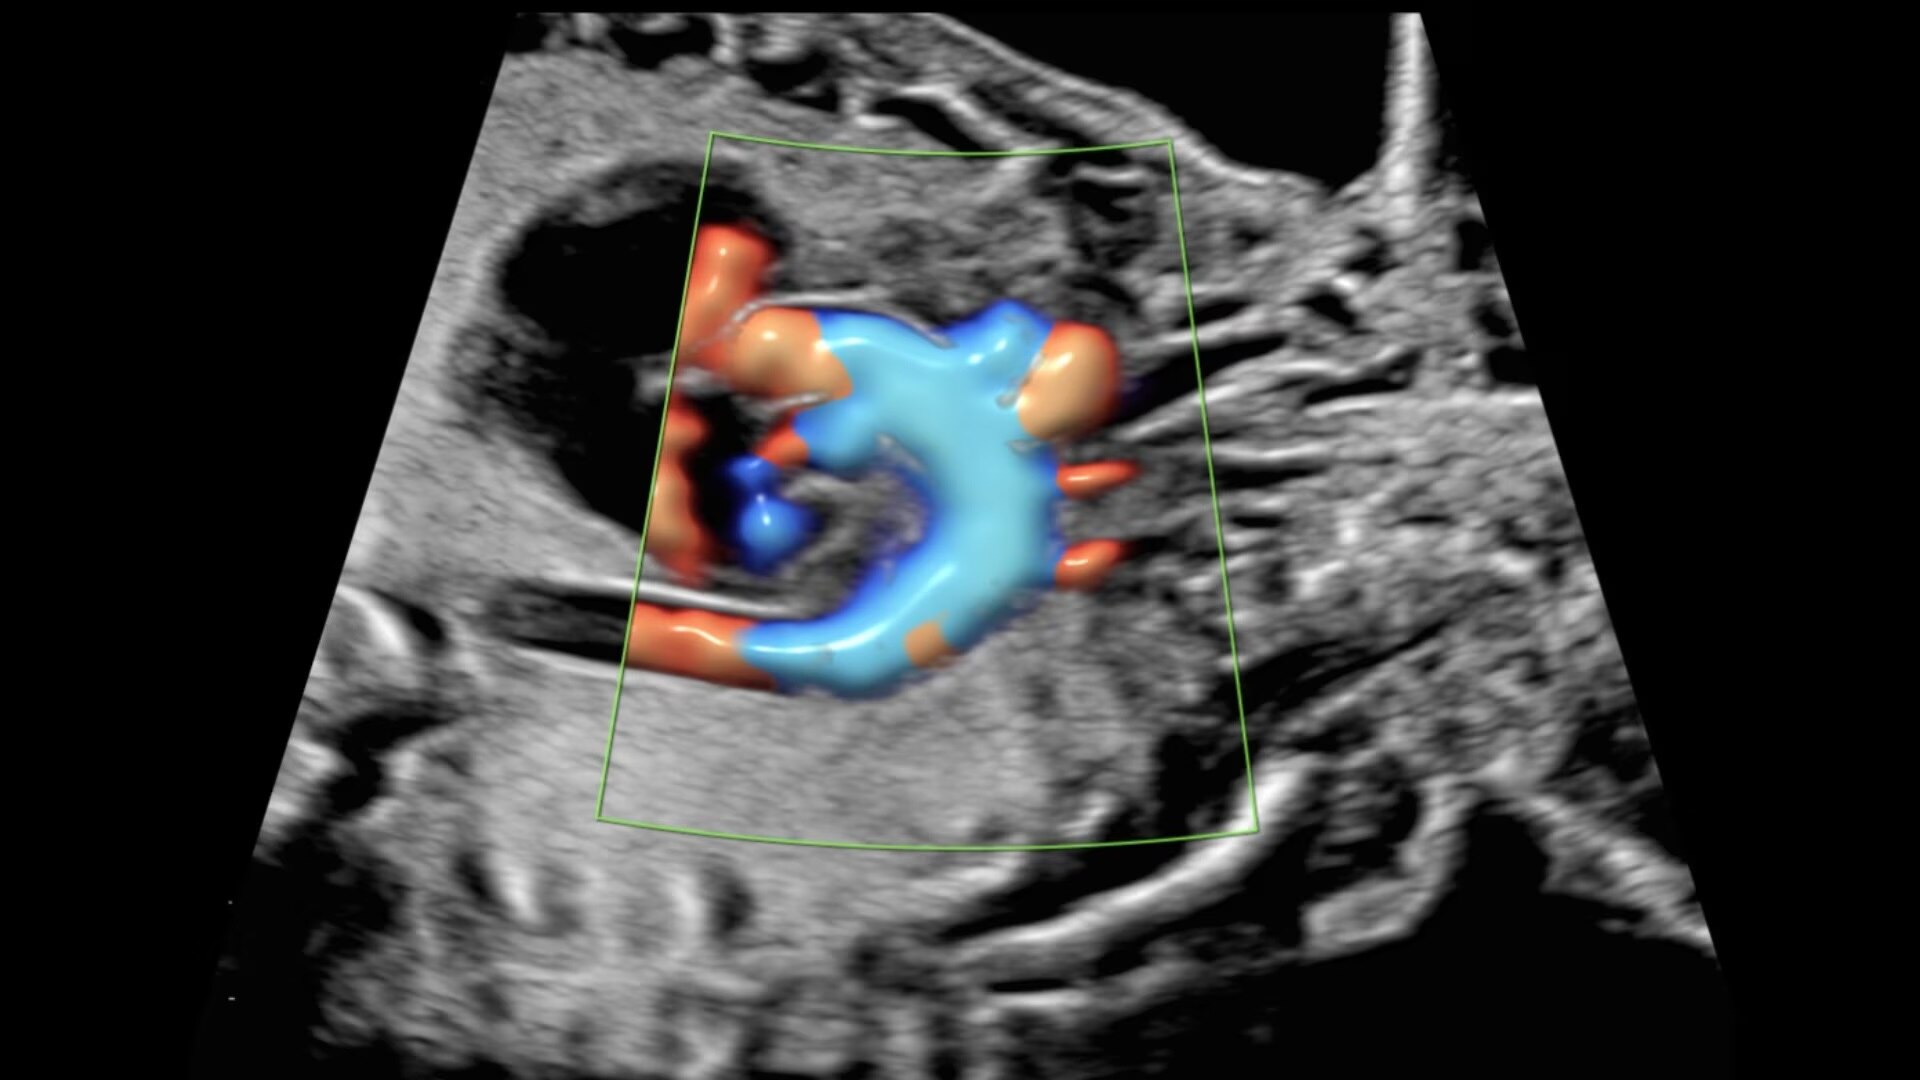

Next level color Doppler for easy, fast visualization of blood flow, displaying a 3D-like appearance.

Uses Color Doppler amplitude to create a 3D-like appearance, helping to clearly separate blood vessels with less flash artifact, improving vessel edge clarity. Available in all color modes, Radiantflow can also be combined with other imaging techniques like spectral Doppler and color M-mode, making it especially useful for visualizing major vessels such as the 3-vessel view (3VV), umbilical cord, arotic arch, and more.